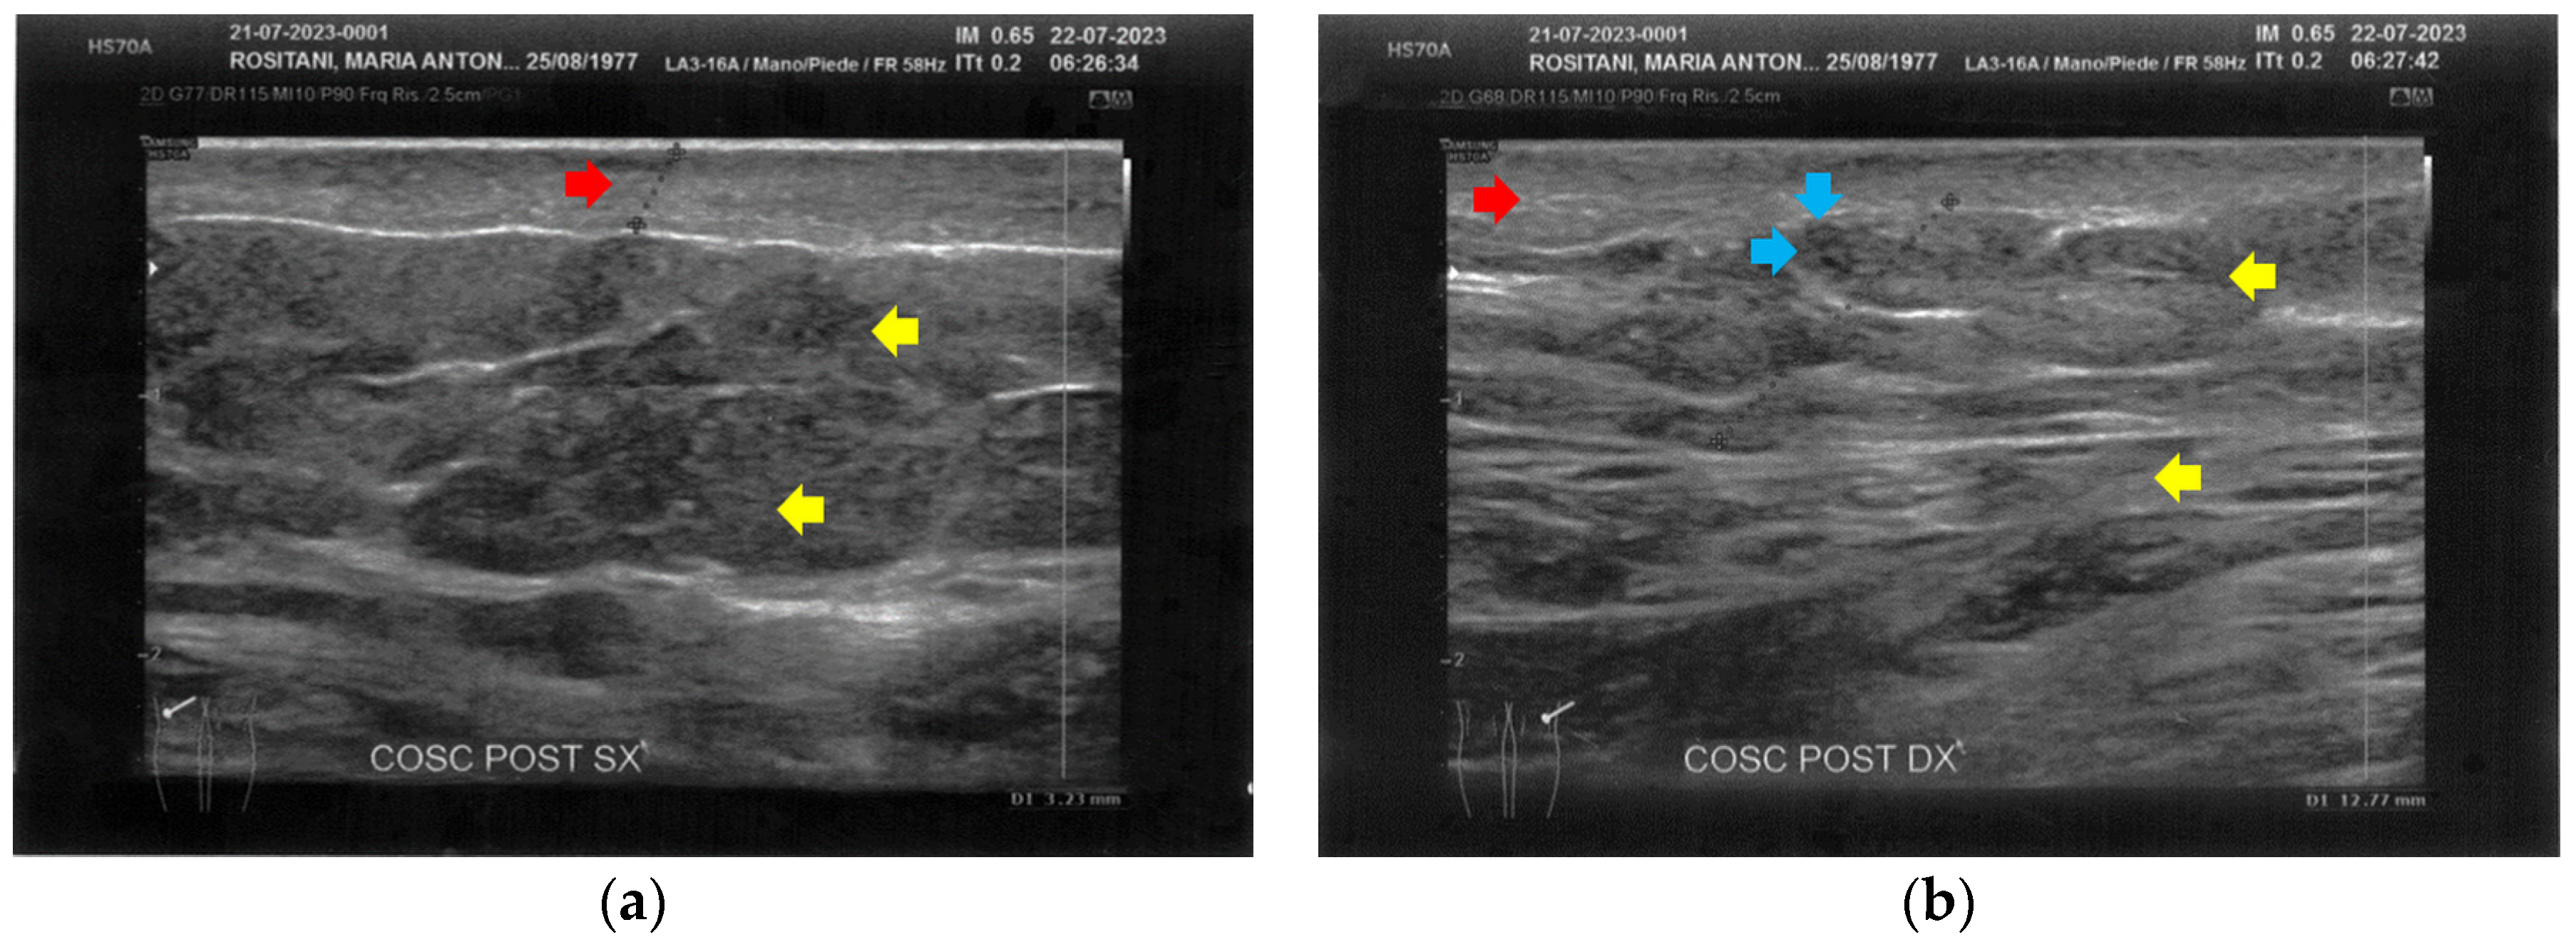

The posterior thighs presented diffuse cicatricial fibrosis and a destructuration of deeper layers (Figure 5).

Figure 5.

Ultrasonography of the posterior thighs at T0. (a) On the left thigh, cicatricial fibrosis (red arrows) is evident on the superficial layers, and phlogosis extends to the deeper layers (yellow arrows); (b) On the right thigh, cicatricial fibrosis (red arrows) is present as on the left side, and the deeper layers present an inhomogeneous restructuring (yellow arrows).

In all the areas tested, superficial vascular elements were absent.